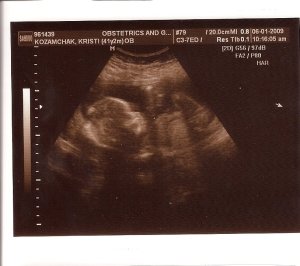

4. We found out we are having a girl! After my “Conspiracy Theory” posting, Joe laughed and said I can now shop with freedom knowing that girls clothing is out there for my buying pleasure. But, in case you think I am going on a complete, out-of-control shopping spree, I will let you know that my sister immediately called and let me know she would be sending boxes of clothing from her girls to me (love saving money!).